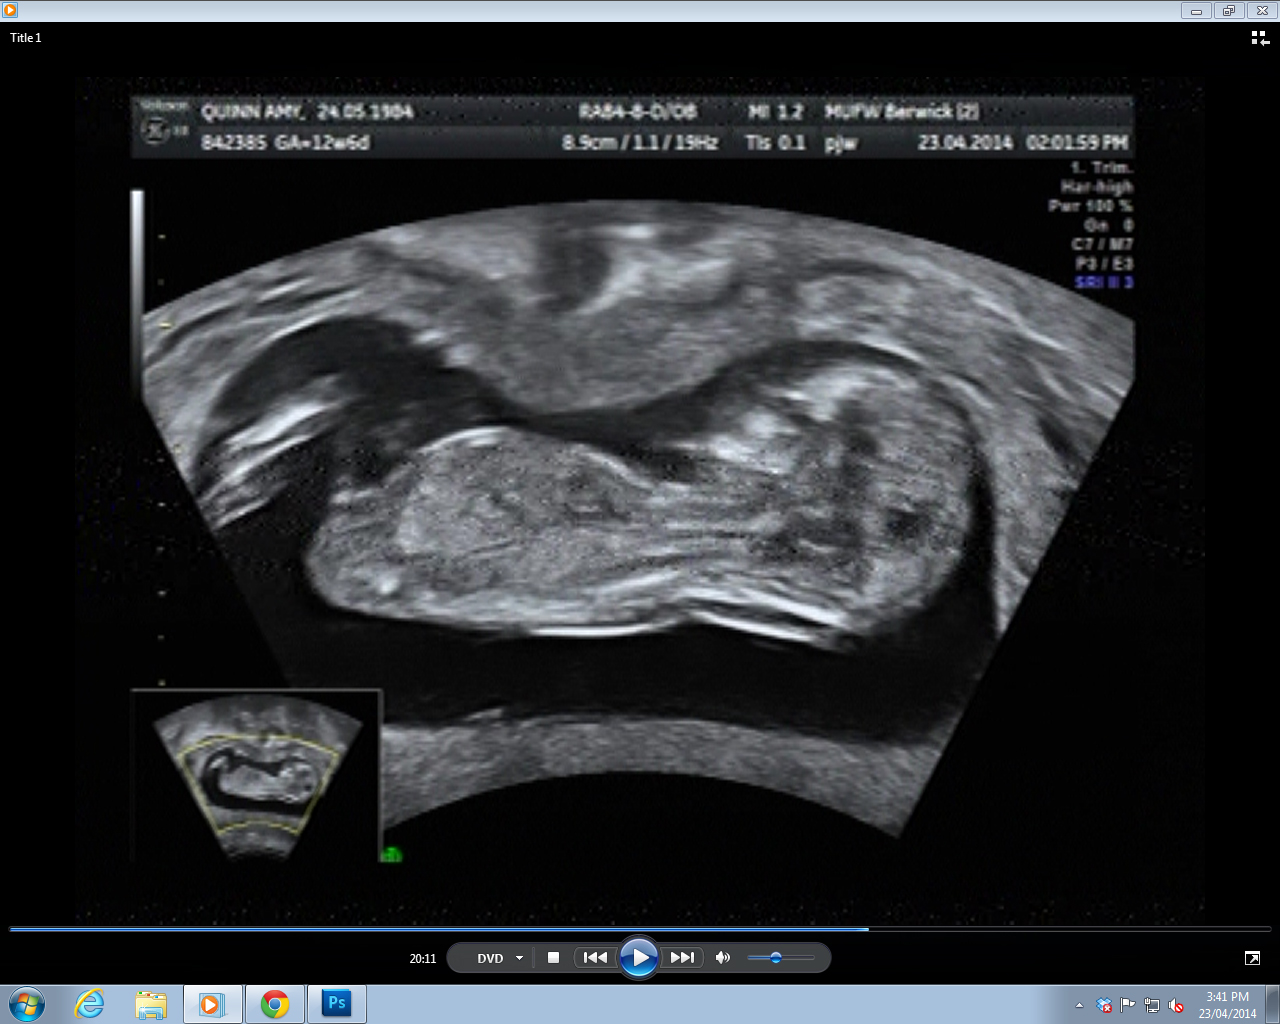

Potty shot 2 - bub has one heck of a full bladder. Just like Mummy...

Attachment 18367

...it's a boy, isn't it?